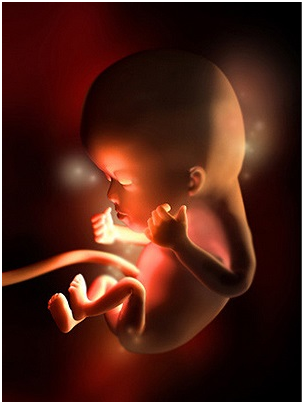

怀孕第28周胎儿图 从现在开始,你就进入了孕晚期,要注意的事情很多呦!你要每天做胎动...

怀孕第28周胎儿图 从现在开始,你就进入了孕晚期,要注意的事情很多呦!你要每天做胎动... -